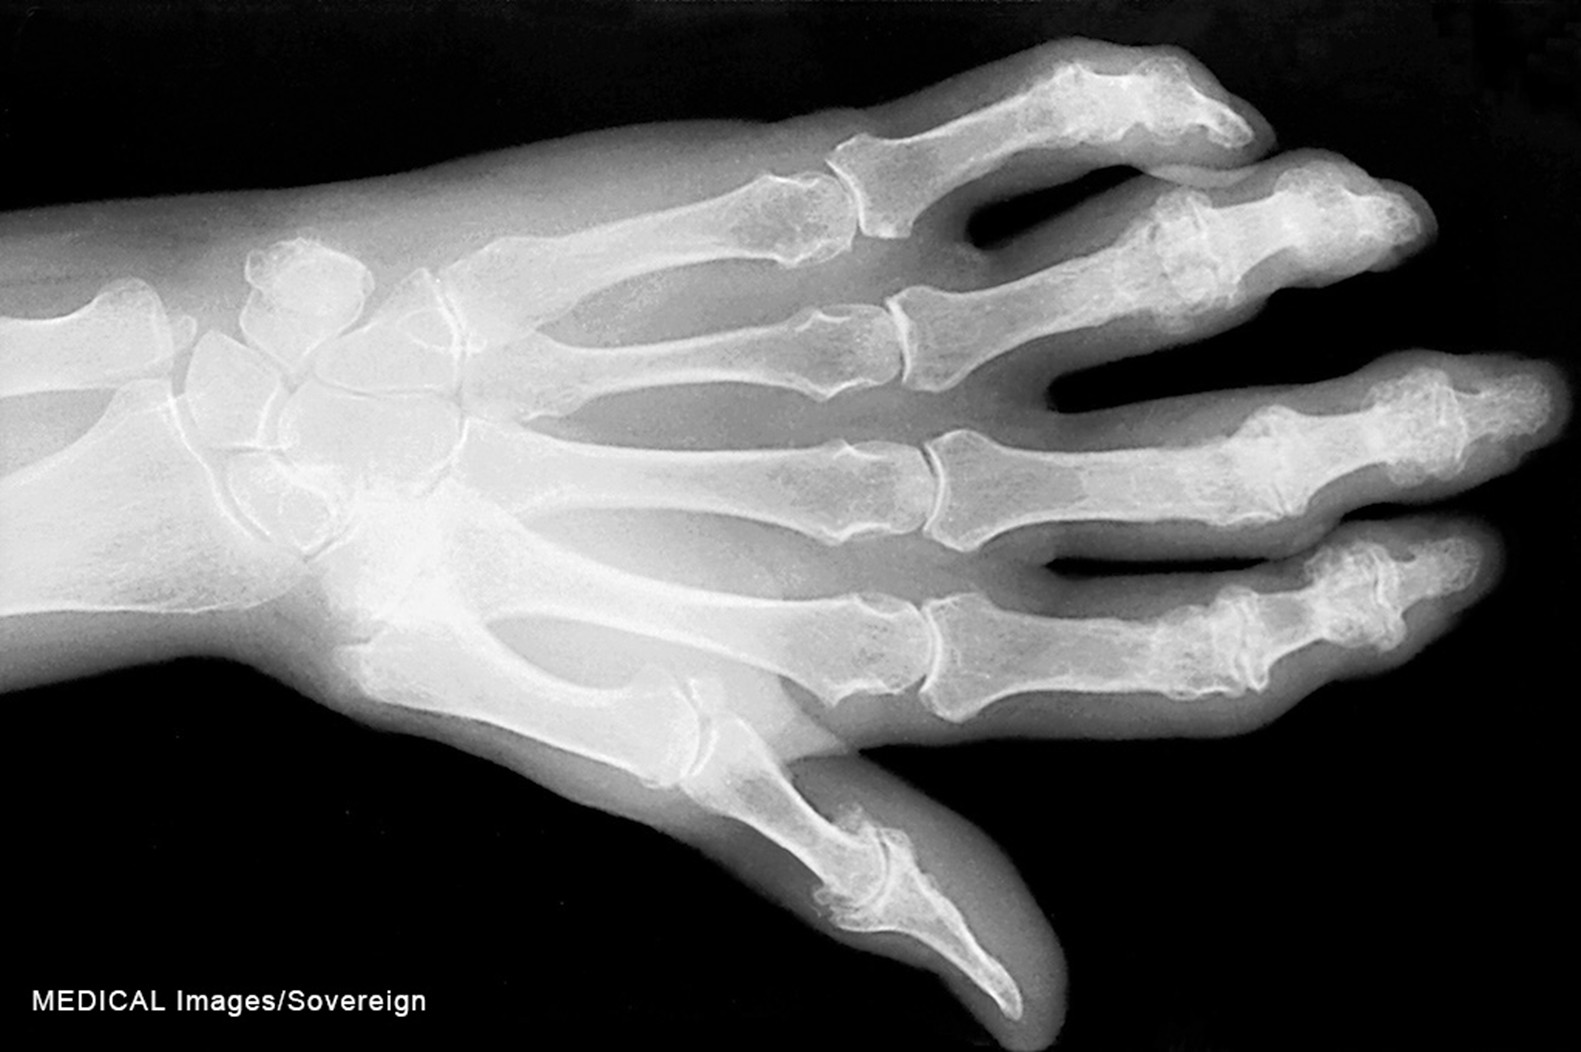

While OA may have unilateral joint involvement, individuals with RA characteristically have bilateral joint involvement and disability. Most causes have an insidious onset, while a smaller percentage, around 15%, may present with an acute onset (Rogers, 2023). Systemic signs and symptoms such as fever, weakness, fatigue, weight loss, and generalized aches and stiffness are typically the first presentation, followed by more local signs and symptoms such as joint tenderness, pain, and stiffness (CDC, 2024b; Rogers, 2023). Joint stiffness in the morning, commonly caused by synovitis, may last 30 minutes to several hours. The most common sites of RA include the wrists, metacarpophalangeal joints, and proximal interphalangeal joints. RA affects these smaller joints initially, followed by larger joints as the condition progresses (Rogers, 2023). The hands may become deformed, and patients may exhibit swan-neck deformities and ulnar deviation due to edema, joint destruction, or subluxation (refer to Figure 4; England, 2025; Rogers, 2023). In addition, patients may experience Boutonniere deformities, which present with hyperextension of the distal interphalangeal joints and flexion of the proximal interphalangeal joints. Over time, with long-standing RA, the cervical spine may become impacted, causing neck discomfort, occipital headaches, and muscle weakness in the upper arms (England, 2025).

Figure 4

Swan-neck deformity